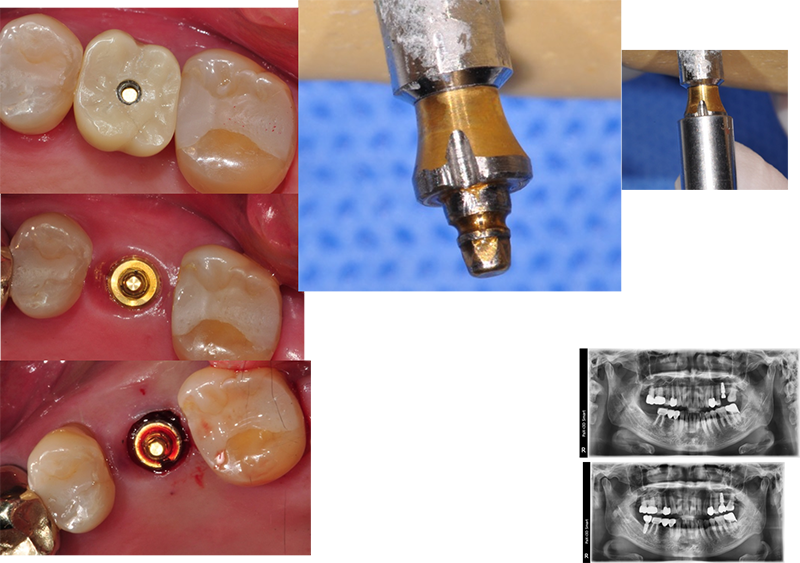

수술하고 바로 convertible abutment인 Ezc ab를

장착하고 인상을 채득했다. 임시보철물을 만들기 위해서다.

Ezc convertible

abutment를 위치시킬 때 수술 직후이므로 잇몸보다 1.0~1.5mm 하방에 위치시키면 좋겠다.

Abutment level

impression(fixture level impression이 아니고) 즉 지대주 레벨 인상이다. 물론 보철도 지대주 레벨의 보철 디자인이 될

마진을 잘 재현하는 한 가지 tip이다

실린더를 픽업(pick-up)(엄밀한 의미에서는 transfer (트란스퍼))해서 러버 인상체에 ‘재 위치’시킨다.

Polysiloxan light

body impression material를 짜

넣는다. 잇몸에 가려졌던 마진이 재현된다. 임플란트의 구성품들은 각기

동일한 규격을 갖고 있다. 임플란트 보철이 쉬운 이유다.

완성된 석고 모형에서 통법대로 보철물을 만들면 된다.